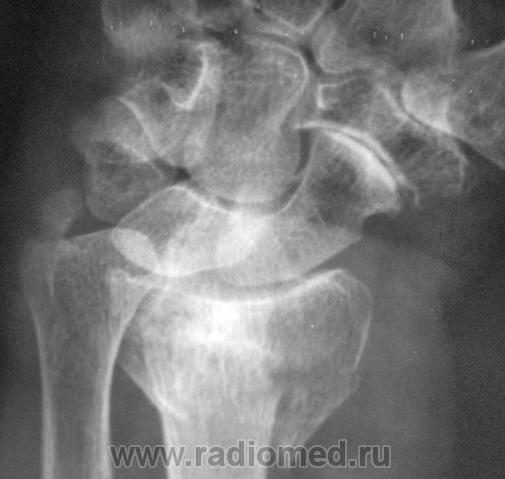

Случай 2.  Пациент направлен врачом хирургом на рентгенографию лучезапястного сустава.

А вот по-поводу второго случая: перелом луча в "типичном" месте, только вот смущает ладьевидная кость - какая-то она патологическая, имеется участок разряжения костной ткани в проекции головки кости или я ошибаюсь?